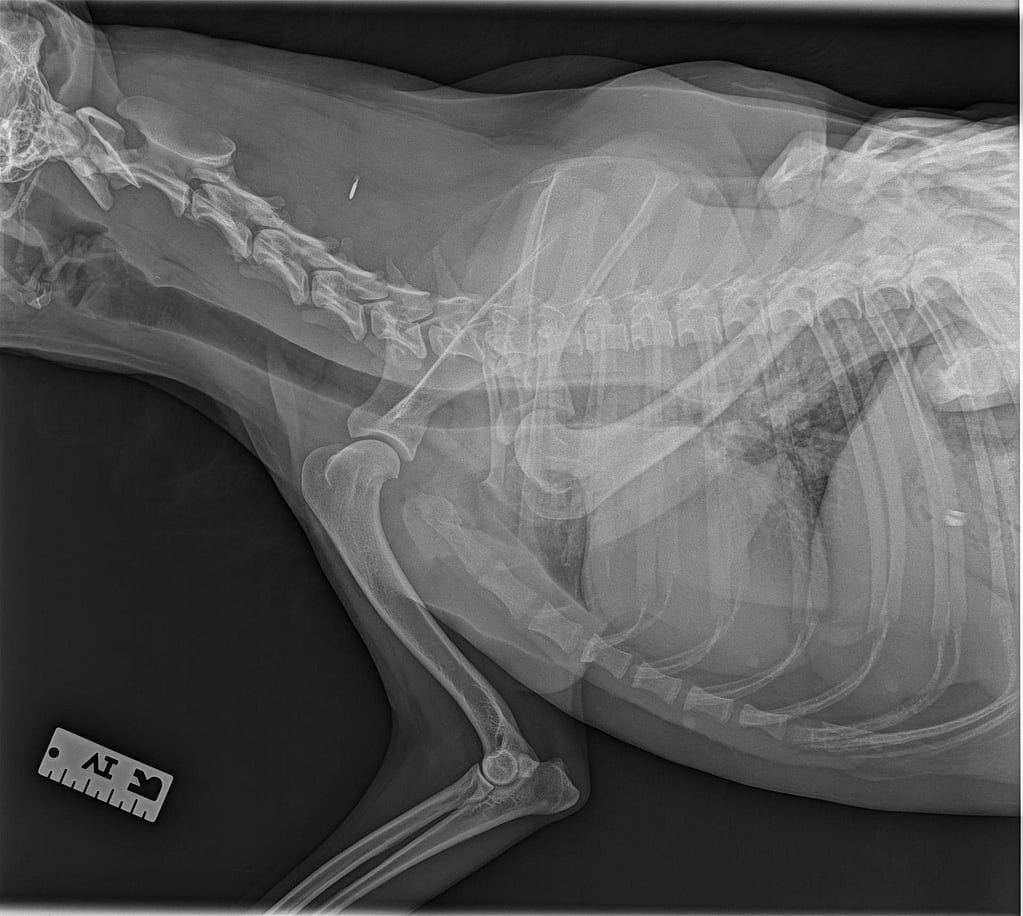

Des radiographies du thorax et du membre thoracique droit ont été réalisées à l’admission (vues latérales et dorso-ventrale).

Les clichés montrent :

- Une luxation latérale évidente de la tête humérale par rapport à la cavité glénoïde.

- Un déplacement de la tête humérale vers l’extérieur, sans fracture humérale ou scapulaire associée.

- Des contours osseux nets, compatibles avec une luxation évoluant depuis plusieurs jours.

- L’absence de lésion thoracique significative.

Ces images confirment la luxation chronique non réductible, orientant vers une stabilisation chirurgicale.